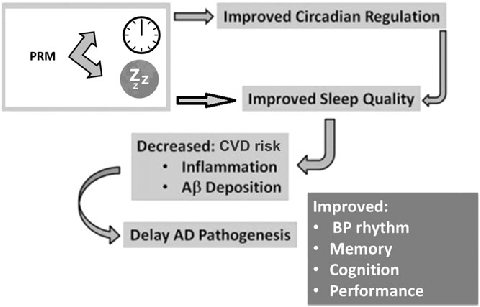

Circadian rhythm regulation involves a complex interplay between the central clock in the suprachiasmatic nuclei and peripheral oscillators throughout the body. Melatonin serves as the primary hormonal signal conveying darkness information to these systems.

Exogenous melatonin administration influences circadian phase positioning, with the direction and magnitude of phase shifts depending on the timing of administration. Evening doses advance the circadian clock, while morning doses may cause phase delays.

Clinical applications of melatonin extend beyond sleep induction to include circadian rhythm resynchronization in jet lag, shift work disorder, and delayed sleep-wake phase disorder. Dose-response relationships vary across these conditions.